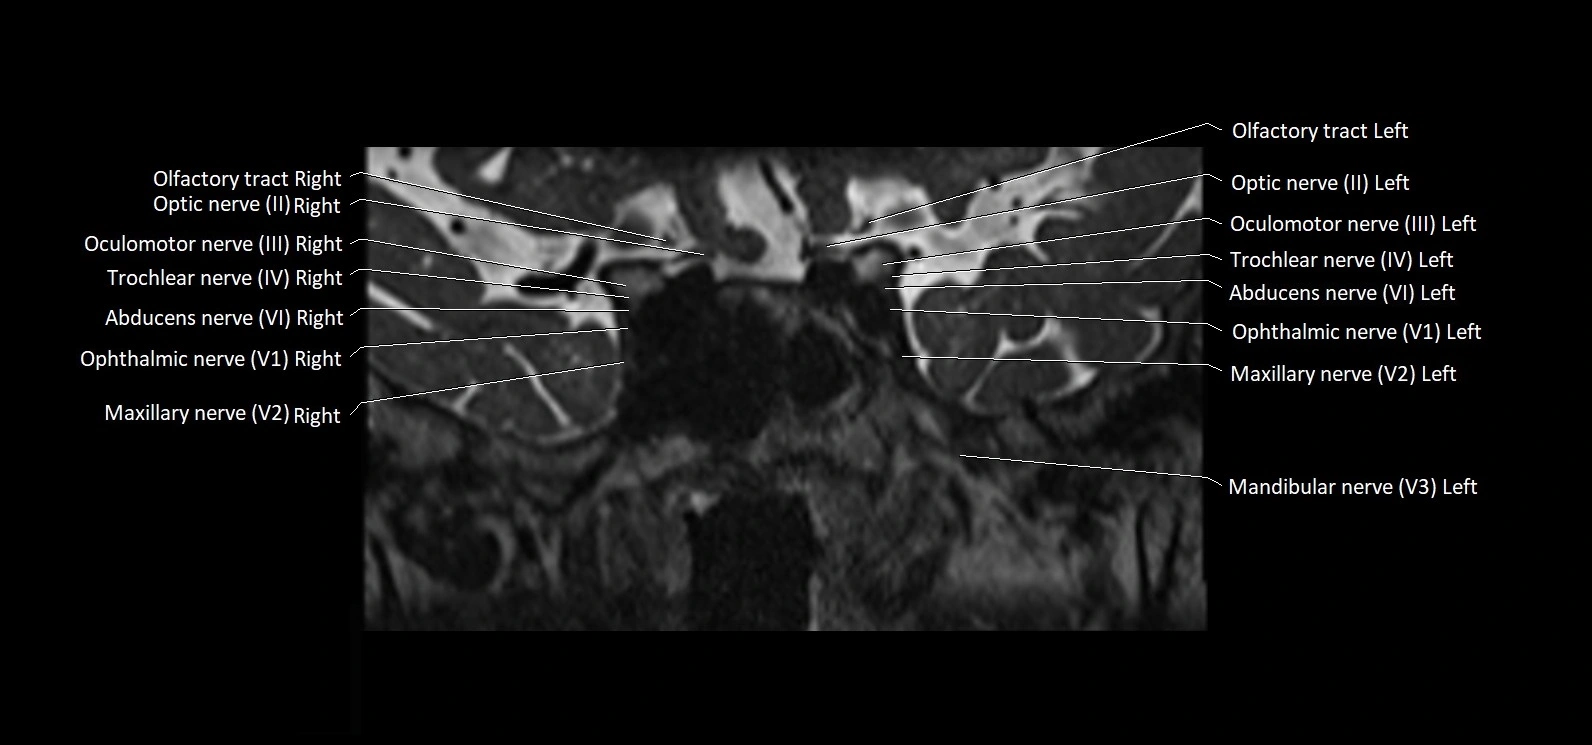

MRI images

image